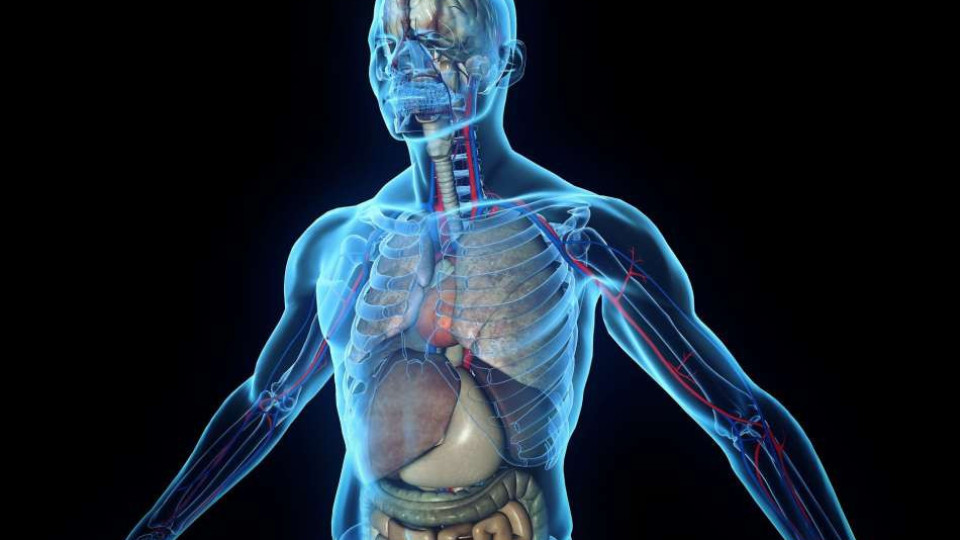

Учени откриха нов орган напълно случайно: Няма да повярвате къде се намира и каква е ролята му:

Бихте си помислили, че вече знаем почти всичко, което трябва да знаем за човешкото тяло, но винаги има още какво да открием, като нов орган например.

Точно това направи екип от изследователи от Холандия, когато през септември 2020 г. откриха, че имаме напълно различен орган и го откриха съвсем случайно, докато изучаваха рака на простатата. Оказва се, че този скрит орган е бил точно под носа ни през цялото време, или по-скоро точно зад него.

Точно така, всъщност е в собствената ни глава, точно под лицето. В този момент може би се чудите как екип, изучаващ рак на простатата, е открил орган в човешката глава, като се има предвид, че това са два различни края на тялото.

Всичко се обърка, след като учените по рака проведоха серия от CT и PET сканирания на пациенти, които са били инжектирани с радиоактивна глюкоза, която кара туморите да светят на изображенията. Екипът от Холандския онкологичен институт разбра, че две области в главите на пациентите са ужасно ярки и заключи, че там са скрити редица слюнчени жлези.

Изобретателите нарекоха органа тубарни слюнчени жлези и те се намират зад носа; в ъгъла, където носната кухина се среща с гърлото. Що се отнася до този случайно открит орган, той трябва да „смазва и овлажнява областта на гърлото зад носа и устата“.

Откриването на жлезите дойде като шок за учените, оставяйки експертите в недоумение как е възможно те по някакъв начин да останат неоткрити толкова дълго. д-р Вутер Фогел, радиационен онколог в Холандския онкологичен институт, каза, че най-вероятните причини, поради които са останали скрити толкова дълго, е, че изискват „много чувствително изображение“, за да ги забележат, и „не са много достъпни“.

Откритие от голямо значение

Той каза: „Хората имат три групи големи слюнчени жлези, но те не са там. Доколкото ни е известно, единствените слюнчени жлези или лигавици в назофаринкса са микроскопично малки, като до 1000 от тях са равномерно разпределени по лигавицата. Така че представете си нашата изненада, когато ги намерихме.“

Откриването на този орган може да помогне да се обясни защо хората, подложени на лъчетерапия, страдат от сухота в устата и проблеми с преглъщането след това. д-р Фогел каза, че „един неправилно насочен удар“ може да увреди трайно органа и фактът, че не са знаели, че съществуват, означава, че „никой не се е опитвал да ги спаси преди“.

Въпреки че откритието е случайно, учените се надяват, че с течение на времето техните открития ще помогнат на пациентите с рак да изпитват по-малко усложнения след лъчева терапия, тъй като те вярват, че много усложнения, свързани с лечението, са свързани с тубарните слюнчени жлези.

След като вече знаят за този орган, „следващата стъпка“ е да разберат как да избегнат увреждане по време на лъчетерапия. Ако експертите успеят да го открият, това може да доведе до значително подобряване на качеството на живот на хората, които се нуждаят от лъчетерапия.